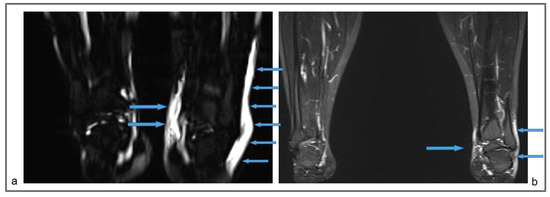

Figure 5.

Patient 2: Preoperative (a) and follow-up (b) non-contrast MR lymphography, 1 year after the surgical procedure, based on high-resolution heavily T2-weighted coronal sequences (turbo spin echo with repetition time 2870 ms, echo time 797 ms, field of view 380 × 380 mm, matrix 358 × 384, slice thickness 1 mm). The follow-up lymphography demonstrates the creation of new inguinal lymphatic vessels (b; blue arrows), that were not visible at the first examination (a).

For a comparison (Figure 10), we also show the preoperative MR lymphography and 1-year follow-up of a 25-year-old woman affected by a right primary LE, treated with venolymphatic anastomosis. The follow-up imaging showed a decrease in the edema, but no new lymphatic vessels were recognizable.

Figure 10.

Preoperative non-contrast MR lymphography (based on high-resolution heavily T2-weighted coronal sequences (turbo spin echo with repetition time 2870 ms, echo time 797 ms, field of view 380 × 380 mm, matrix 358 × 384, slice thickness 1 mm) (a) and follow-up non-contrast MR lymphography (b) 1-year post-venolymphatic-anastomosis. Marked edema involving the lower third of the leg, the ankle, and the dorsum of the foot (blue arrows) is visible in (a), while follow-up imaging (b) shows a reduction of the edema (blue arrows), but without evidence of any new lymphatic vessels.